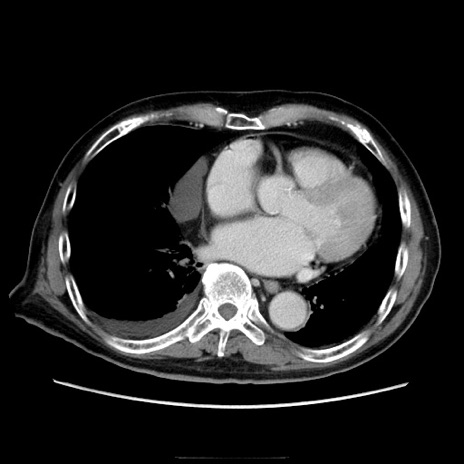

冠状断像

【症例】70歳代男性

【現病歴】肝硬変・肝細胞癌にてかかりつけの方。約9時間前に食後より腹痛出現。症状が徐々に増悪し、嘔吐出現したため来院。

【既往歴】肝硬変、肝細胞癌(RFA、TACE後)